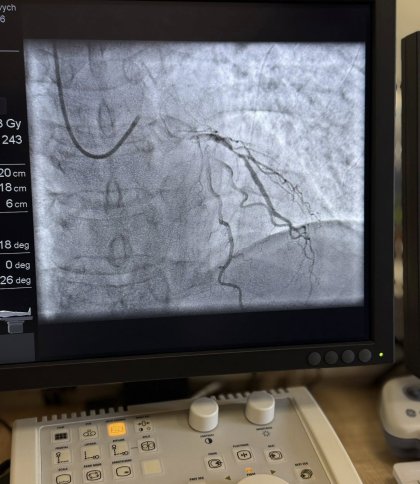

Лікарі виявили, що у пацієнта хронічний коронарний синдром — стан, при якому серце не отримує достатньо крові та кисню через звуження коронарних артерій. Після стабілізації стану пана Ігоря медики прийняли рішення провести операцію — стентування серцевих судин. З цього року така процедура стала безкоштовною для пацієнтів, як і ургентне лікування, завдяки Програмі медичних гарантій, яка покривається державним фінансуванням. Це означає, що саму операцію та необхідні матеріали, зокрема стенти, оплачує держава через Національну службу здоров’я України (НСЗУ).

«Під час операції я перебував у свідомості. Це не надто складне втручання, але дуже приємно, що воно безкоштовне. І зараз я почуваюся значно краще, ніж кілька днів тому», — розповів пан Ігор.